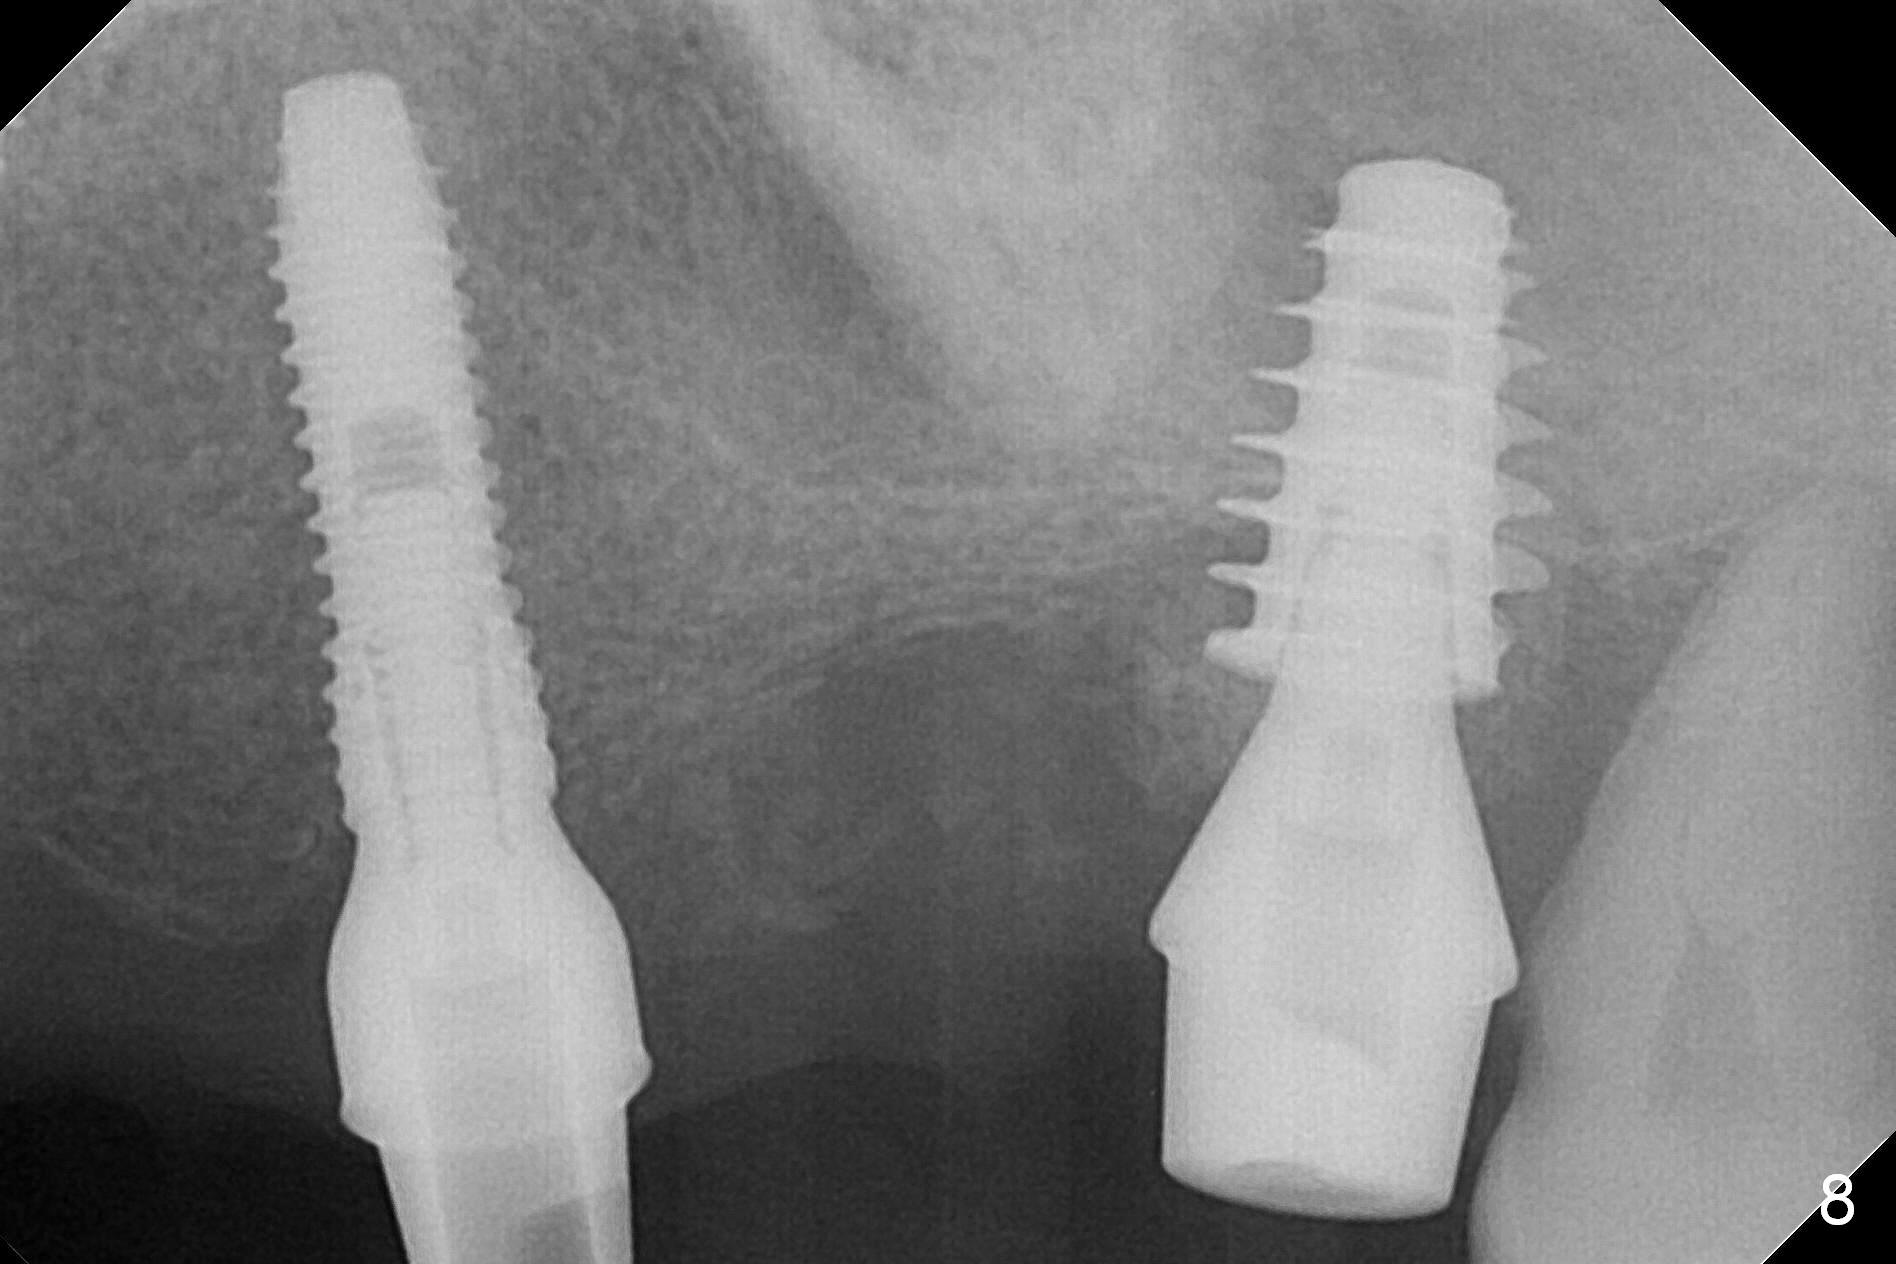

One month later, bone graft is placed mesiopalatal to the implant at #15 (Fig.7 *,8) while a 3.8x13 mm implant is placed at #13 following bone expansion (using Magic Split and Magic Expander 3.0 mm (abutment 5.5x4(5) mm). Another month later, the tooth #16 is extracted to create space for #15 restoration. Two weeks later the abutment at #15 is found to be unstable (2.5 months postop). Local oral hygiene is poor. The abutment is removed and a 6x4 mm healing abutment is placed with mild tenderness. It appears that the limited bone height is associated with low stability with CMC. Three months later (5.5 months postop), the implant seems to be stable (Fig.9,10). The implant remains stable clinically 7 months postop (Fig.11). The bone graft appears to mature and covers the abutment with provisional 24 months postop, the bony changes is related to the thick gingiva (Fig.12 ^).